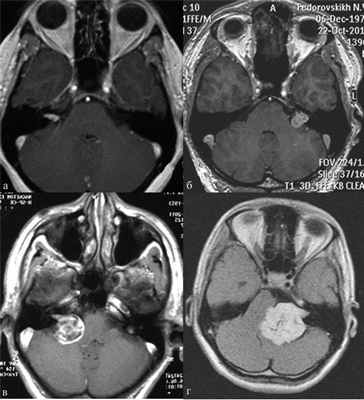

На магнитно-резонансной томографии с гадолинием в аксиальной проекции в режиме Т1 визуализируются двусторонние вестибулярные шванномы,

ассоциированные с НФ2, сдавливающие ствол головного мозга и смещающие его в сторону от срединной линии.

В практической деятельности наиболее универсальными являются классификации, предложенные Koos [11] и Samii [12]. Они основаны на оценке размеров невриномы и ее отношении к окружающим мозговым и костным структурам (рис. 1, 2).

Рис. 1.Иллюстрация классификации неврином слухового нерва по Koos. а — I стадия — опухоль находится в пределах внутреннего слухового прохода, диаметр экстраканальной части составляет 1—10 мм; б — II стадия — опухоль вызывает расширение канала внутреннего слухового прохода и выходит в мостомозжечковый угол, ее диаметр составляет, 11—20 мм; в — III стадия — опухоль распространяется до ствола головного мозга без его компрессии, диаметр составляет 21—30 мм; г — IV стадия — опухоль вызывает компрессию ствола головного мозга, ее диаметр более 30 мм.

Рис. 2.Классификация неврином слухового нерва по M. Samii. а — Т1 — интрамеатальная опухоль (рис. 2, a); б —Т2 — интра-экстрамеатальная опухоль; в — Т3а — опухоль заполняет мостомозжечковую цистерну; г —Т3b — опухоль распространяется до ствола головного мозга; д —Т4а — опухоль вызывает компрессию ствола; е —Т4b — опухоль грубо деформирует ствол мозга и IV желудочек.